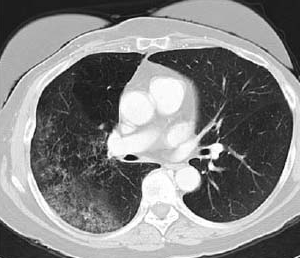

An analysis of data from the National Lung Screening Trial found that more than 18% of all lung cancers detected through low-dose CT screening were indolent.

The USPSTF published its final recommendation on screening for lung cancer on December 31, concluding that all people between the ages of 55 and 80 years who are at high risk for lung cancer should undergo low-dose CT screening.